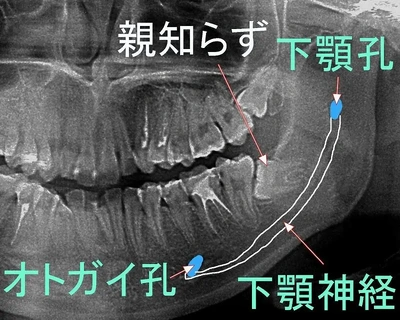

写真のように親知らずの近くに神経が通っているようなので傷ついちゃったみたいです。